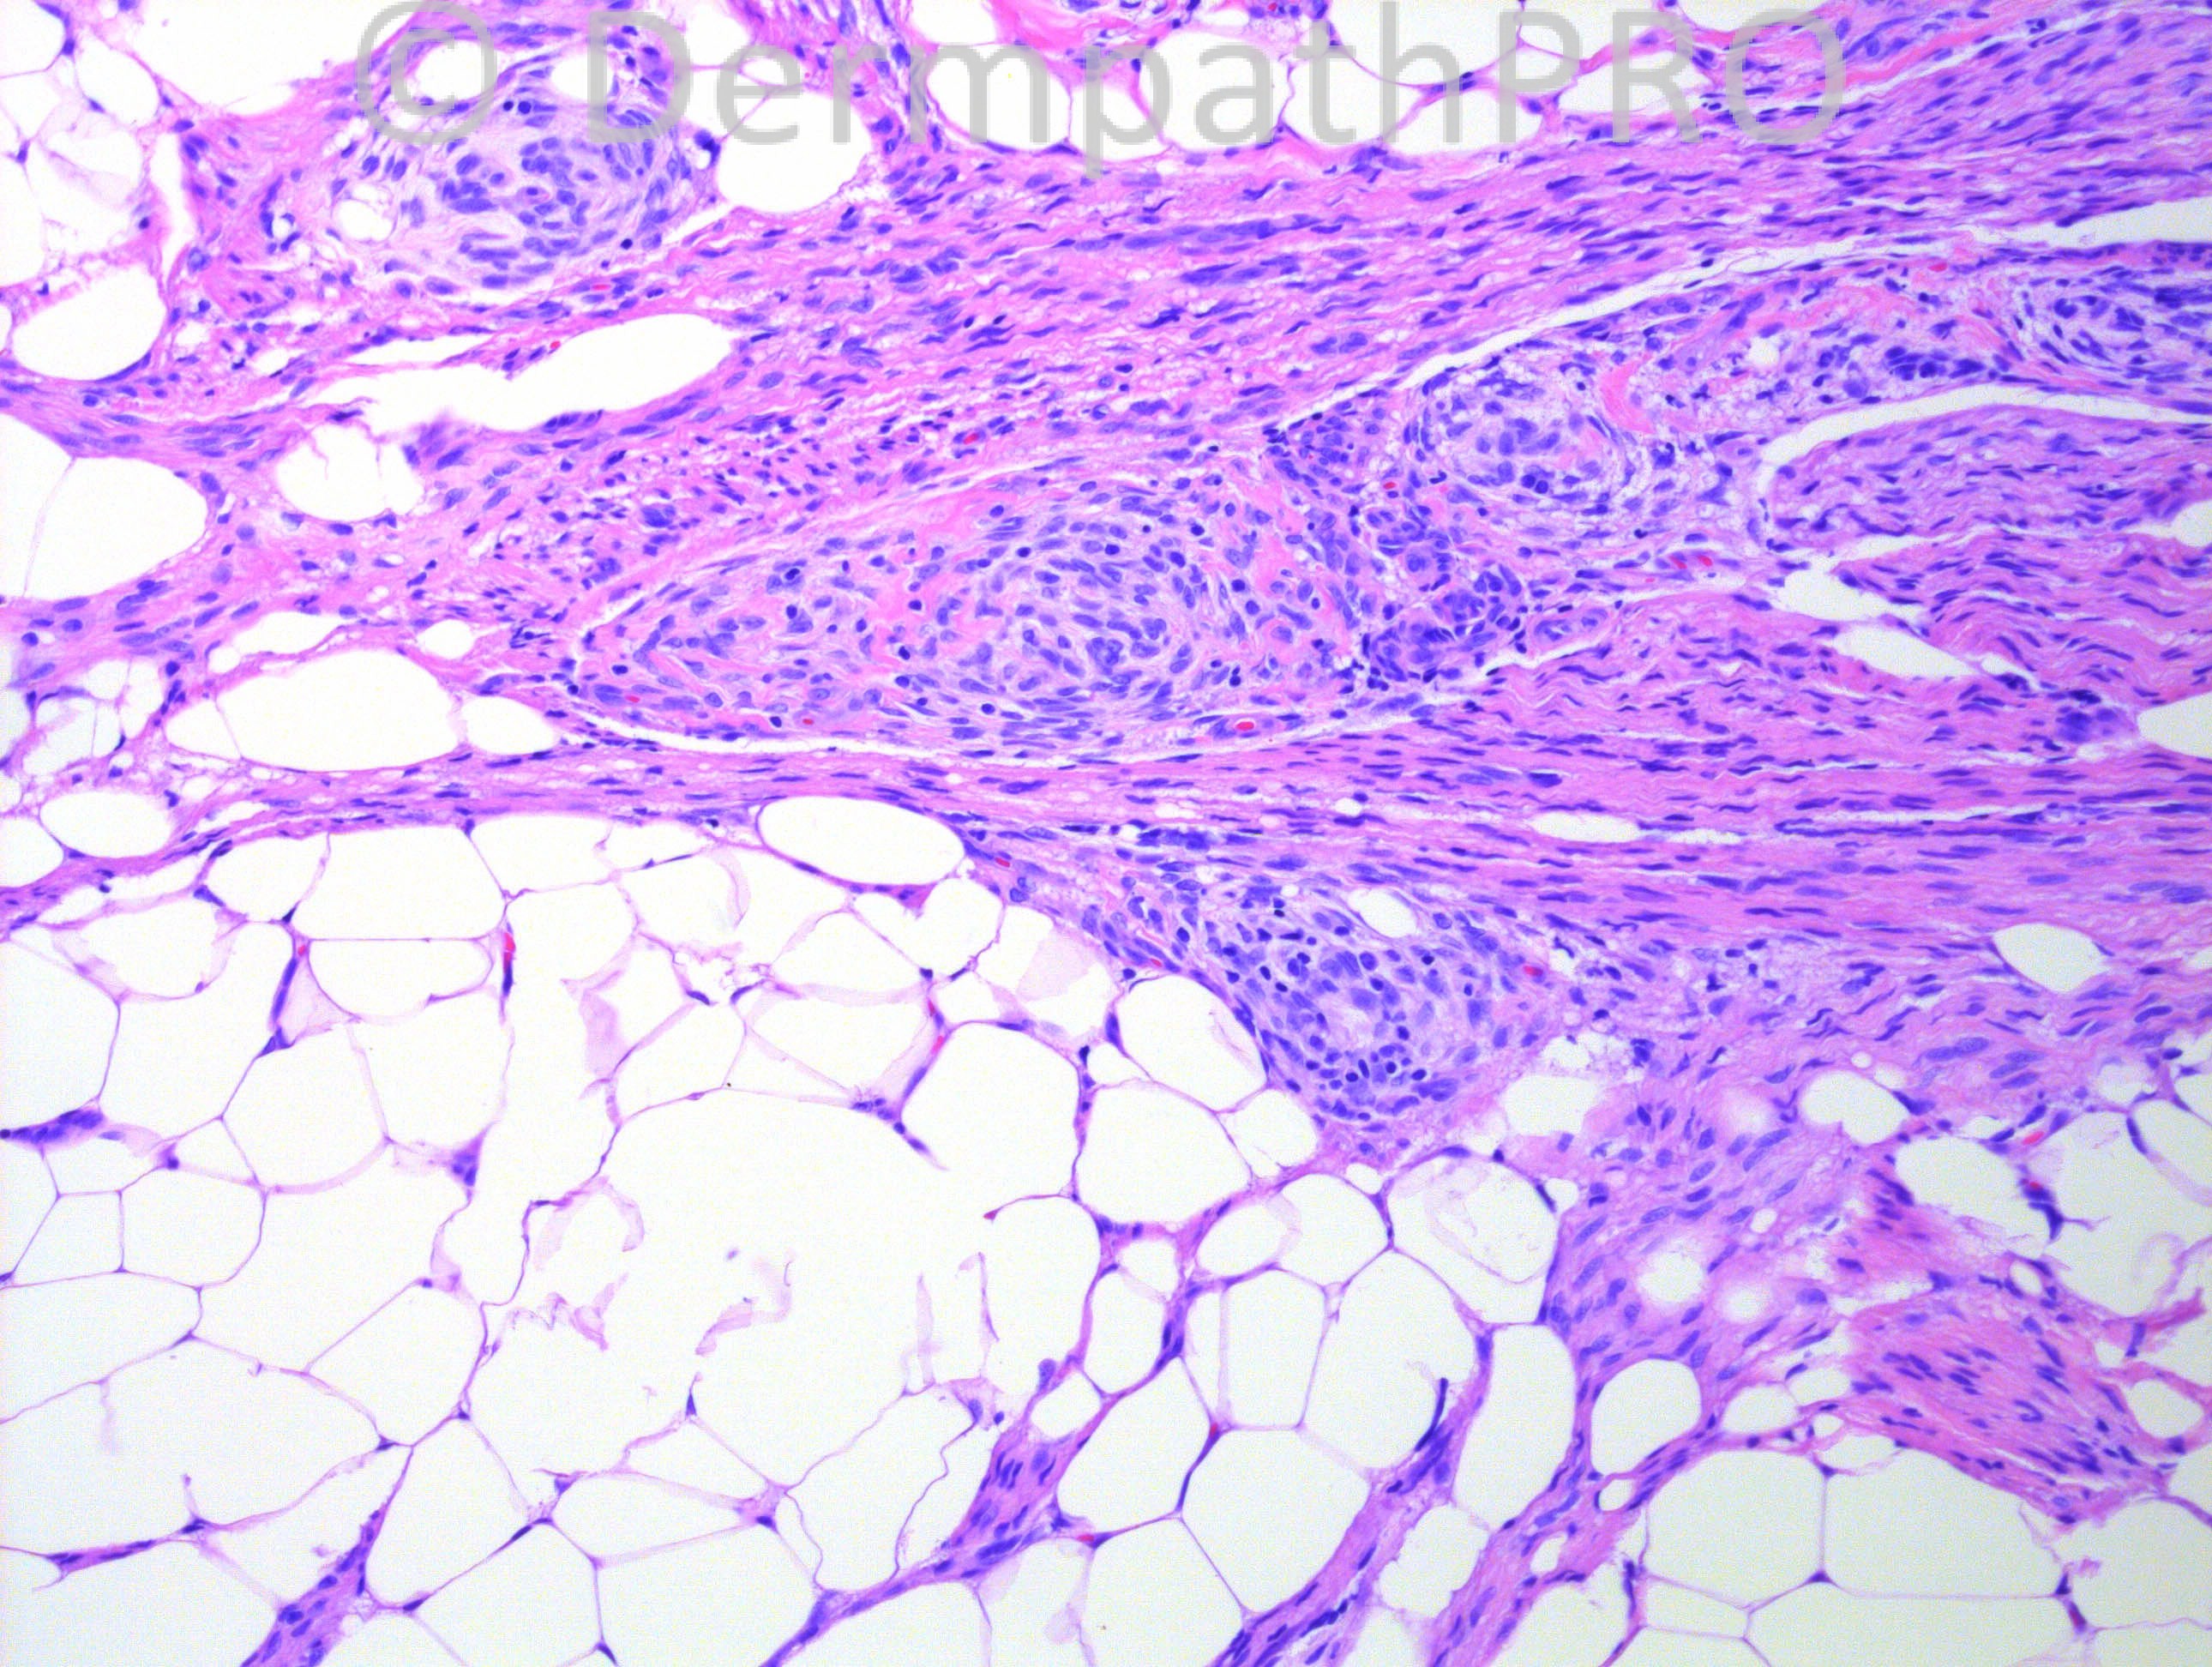

13 months-old Hispanic male with multiple left arm masses.